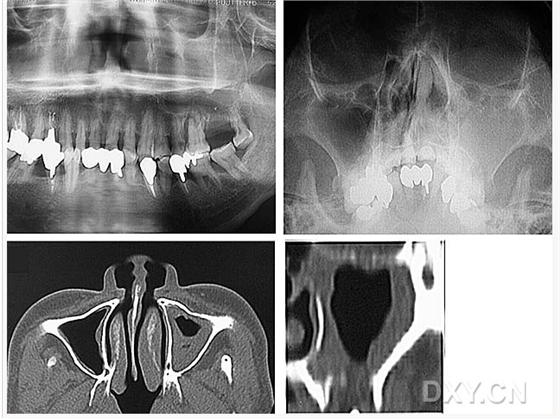

鼻竇炎(注意不要誤診呀)

良性成牙骨質(zhì)細(xì)胞瘤